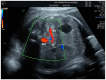

The fetal splenic artery pulsatility index is a parameter that reflects fetal well-being and has been used as a predictor of adverse pregnancy outcomes. The aim of this study was to investigate the predictive value of the splenic artery pulsatility index in gestational diabetes mellitus class A1 cases for intensive care unit admission. In this prospective case-controlled study, only sixty single pregnancy cases diagnosed with gestational diabetes mellitus class A1 were evaluated. Fetal splenic artery Doppler parameters such as peak systolic velocity, pulsatility index, resistivity index, and end-diastolic velocity were measured in all cases. The rate of requirements for the neonatal intensive care unit was noted. In cases requiring fetal intensive care, the fetal splenic pulsatility index was found to be statistically significantly lower than in healthy cases without it (0.94 ± 0.29 vs. 1.70 ± 0.53, respectively, p < 0.001, Student's t-test). When the fetal splenic PI cutoff value was selected as 1.105 cm3, the sensitivity was calculated as 97.9% and the specificity as 58.3% for predicting the need for fetal intensive care (AUC 0.968, p < 0.001, 95% CI 0.929-0.998). The use of a low fetal splenic artery PI parameter is a significant and good indicator for predicting the need for fetal intensive care according to the binary logistic regression analysis result (p = 0.006). This study suggests that evaluation of fetal splenic artery Doppler in mothers with gestational diabetes mellitus may be used to predict neonates requiring a newborn intensive care unit. Therefore, it is recommended that obstetricians use this simple, rapid, and valuable evaluation of fetal splenic artery Doppler and alert the neonatologist that a newborn intensive care unit may be required.